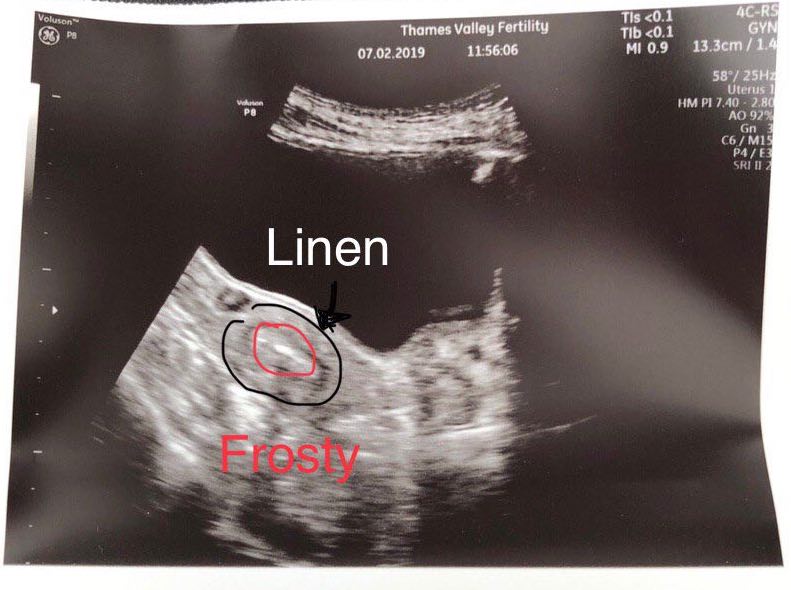

On Feb 7th at 11:30am, the implantation happens. If you have no idea what you’re looking at in the picture above, here are some info to orientate your eyes: